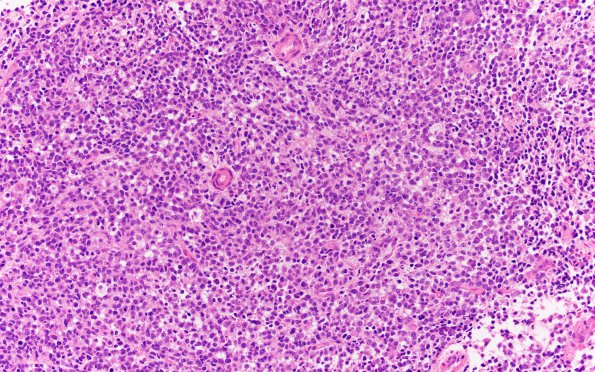

Washington University Experience | NEOPLASMS (EMBRYONAL) | ATRT - Atypical Teratoid Rhabdoid Tumor | 17B2 ATRT (Case 17) H&E 20X 2

Sections of the "posterior fossa tumor" show a diffusely infiltrating small round blue cell tumor with large nuclei, vesicular chromatin pattern and scant cytoplasm. Admixed nests of larger cells with moderate amounts of eosinophilic cytoplasm, vesicular nuclei with prominent nucleoli (rhabdoid cells) are noted. There is increased mitotic activity and abundant necrosis.